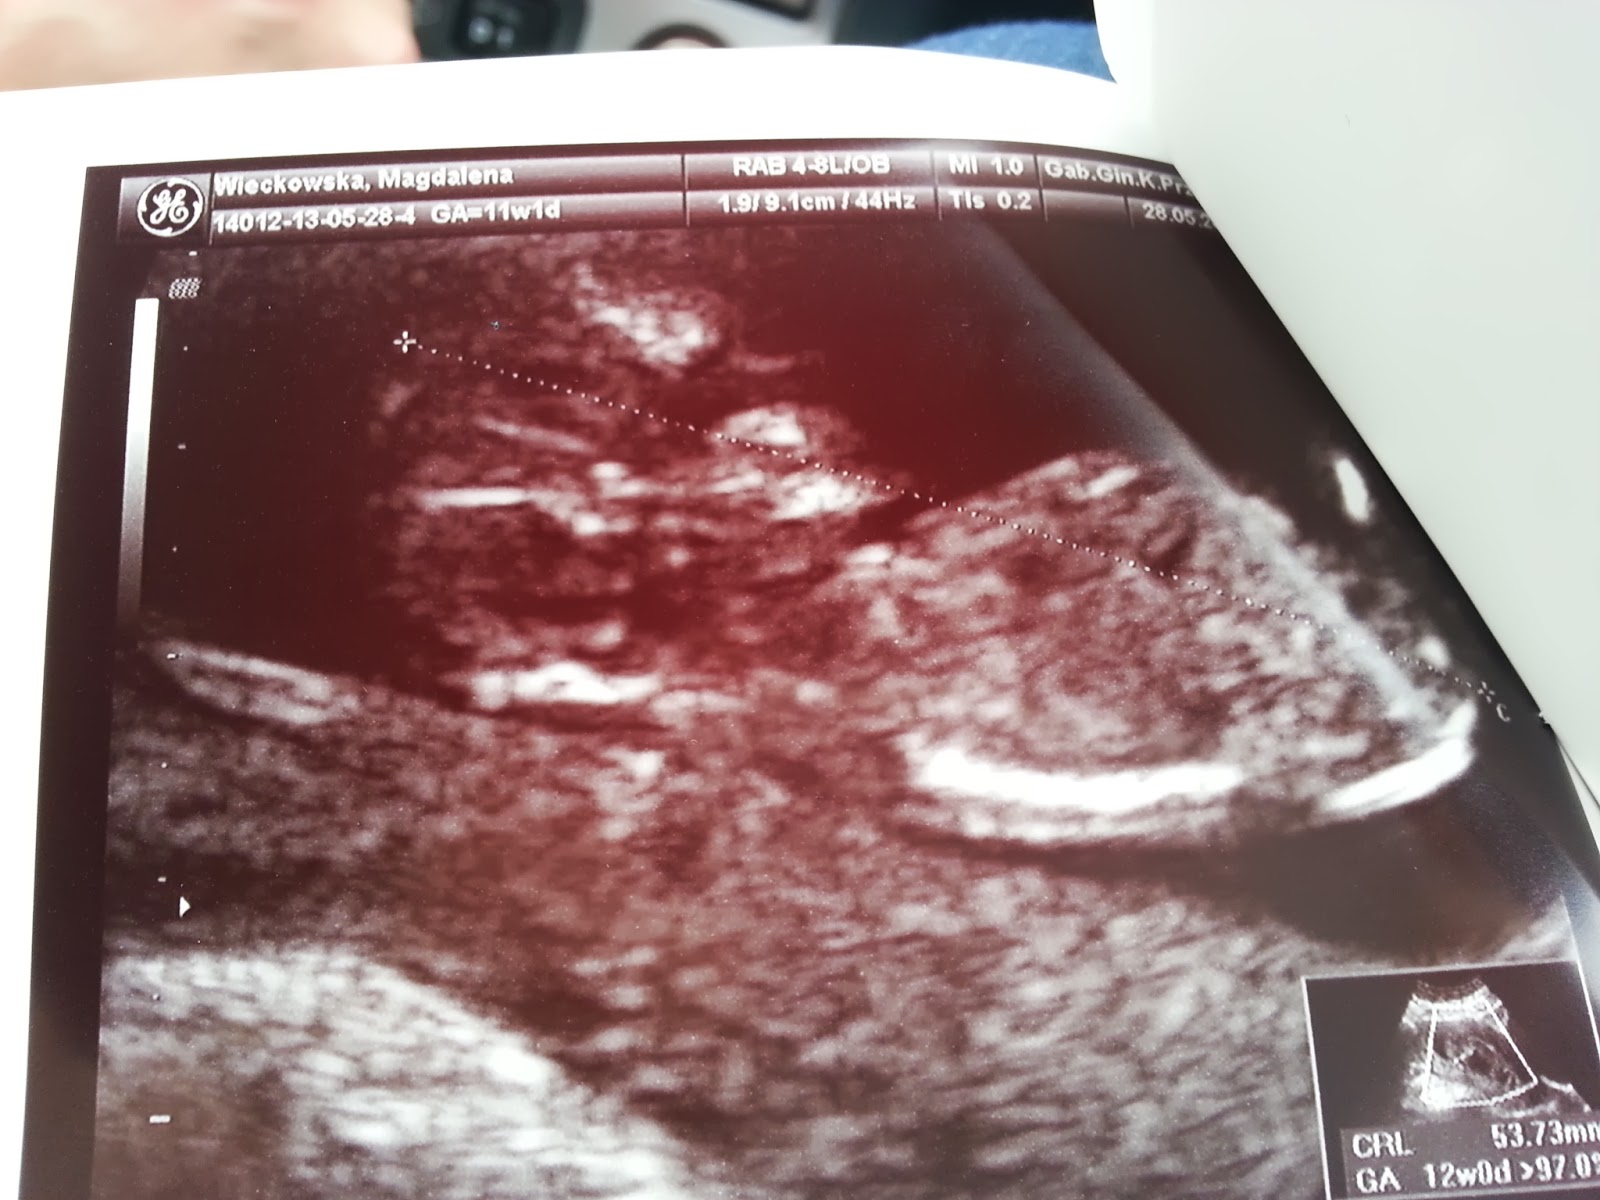

Okazuje się, że nasze Młode, to niezwykle szalone i ruchliwe dziecko. Pani doktor musiała pukać głowicą w brzuch, żeby zmieniło pozycję na lepszą i szybko robić fotki, bo wciąż się wierciło. Dlatego jakość średnia, ale coś tam już można zobaczyć :)

W każdym razie Bąbel zdrowy. Długość (5,3cm) wskazuje na skończony 12tc, także termin coraz bardziej prawdopodobny. Kość nosowa jest, przezierność karkowa 1mm, serducho waliło 150/min. Wszystko pięknie! Zakochani jesteśmy po uszy.

Dobra, koniec tych smutków! Wracamy do cieszenia się! Poniżej dwie fotki, tak jak pisałam wcześniej, niewyraźne. Wytrwali pewnie ujrzą tam ludzką istotę.